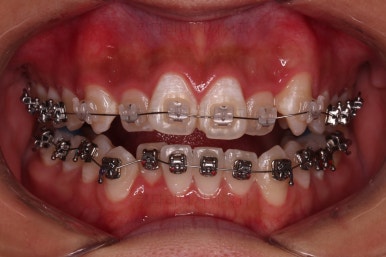

장치를 처음 부착했고요.

이번 환자분이 선택한 장치는 윗니는 세라믹 자가결찰인 엠파워 클리어, 아래는 메탈 자가결찰인 엠파워 메탈입니다. 둘 다 같은 회사의 같은 세팅의 장치이므로 혼용이 가능하죠. 대신 비용은 좀 더 줄일 수 있습니다.